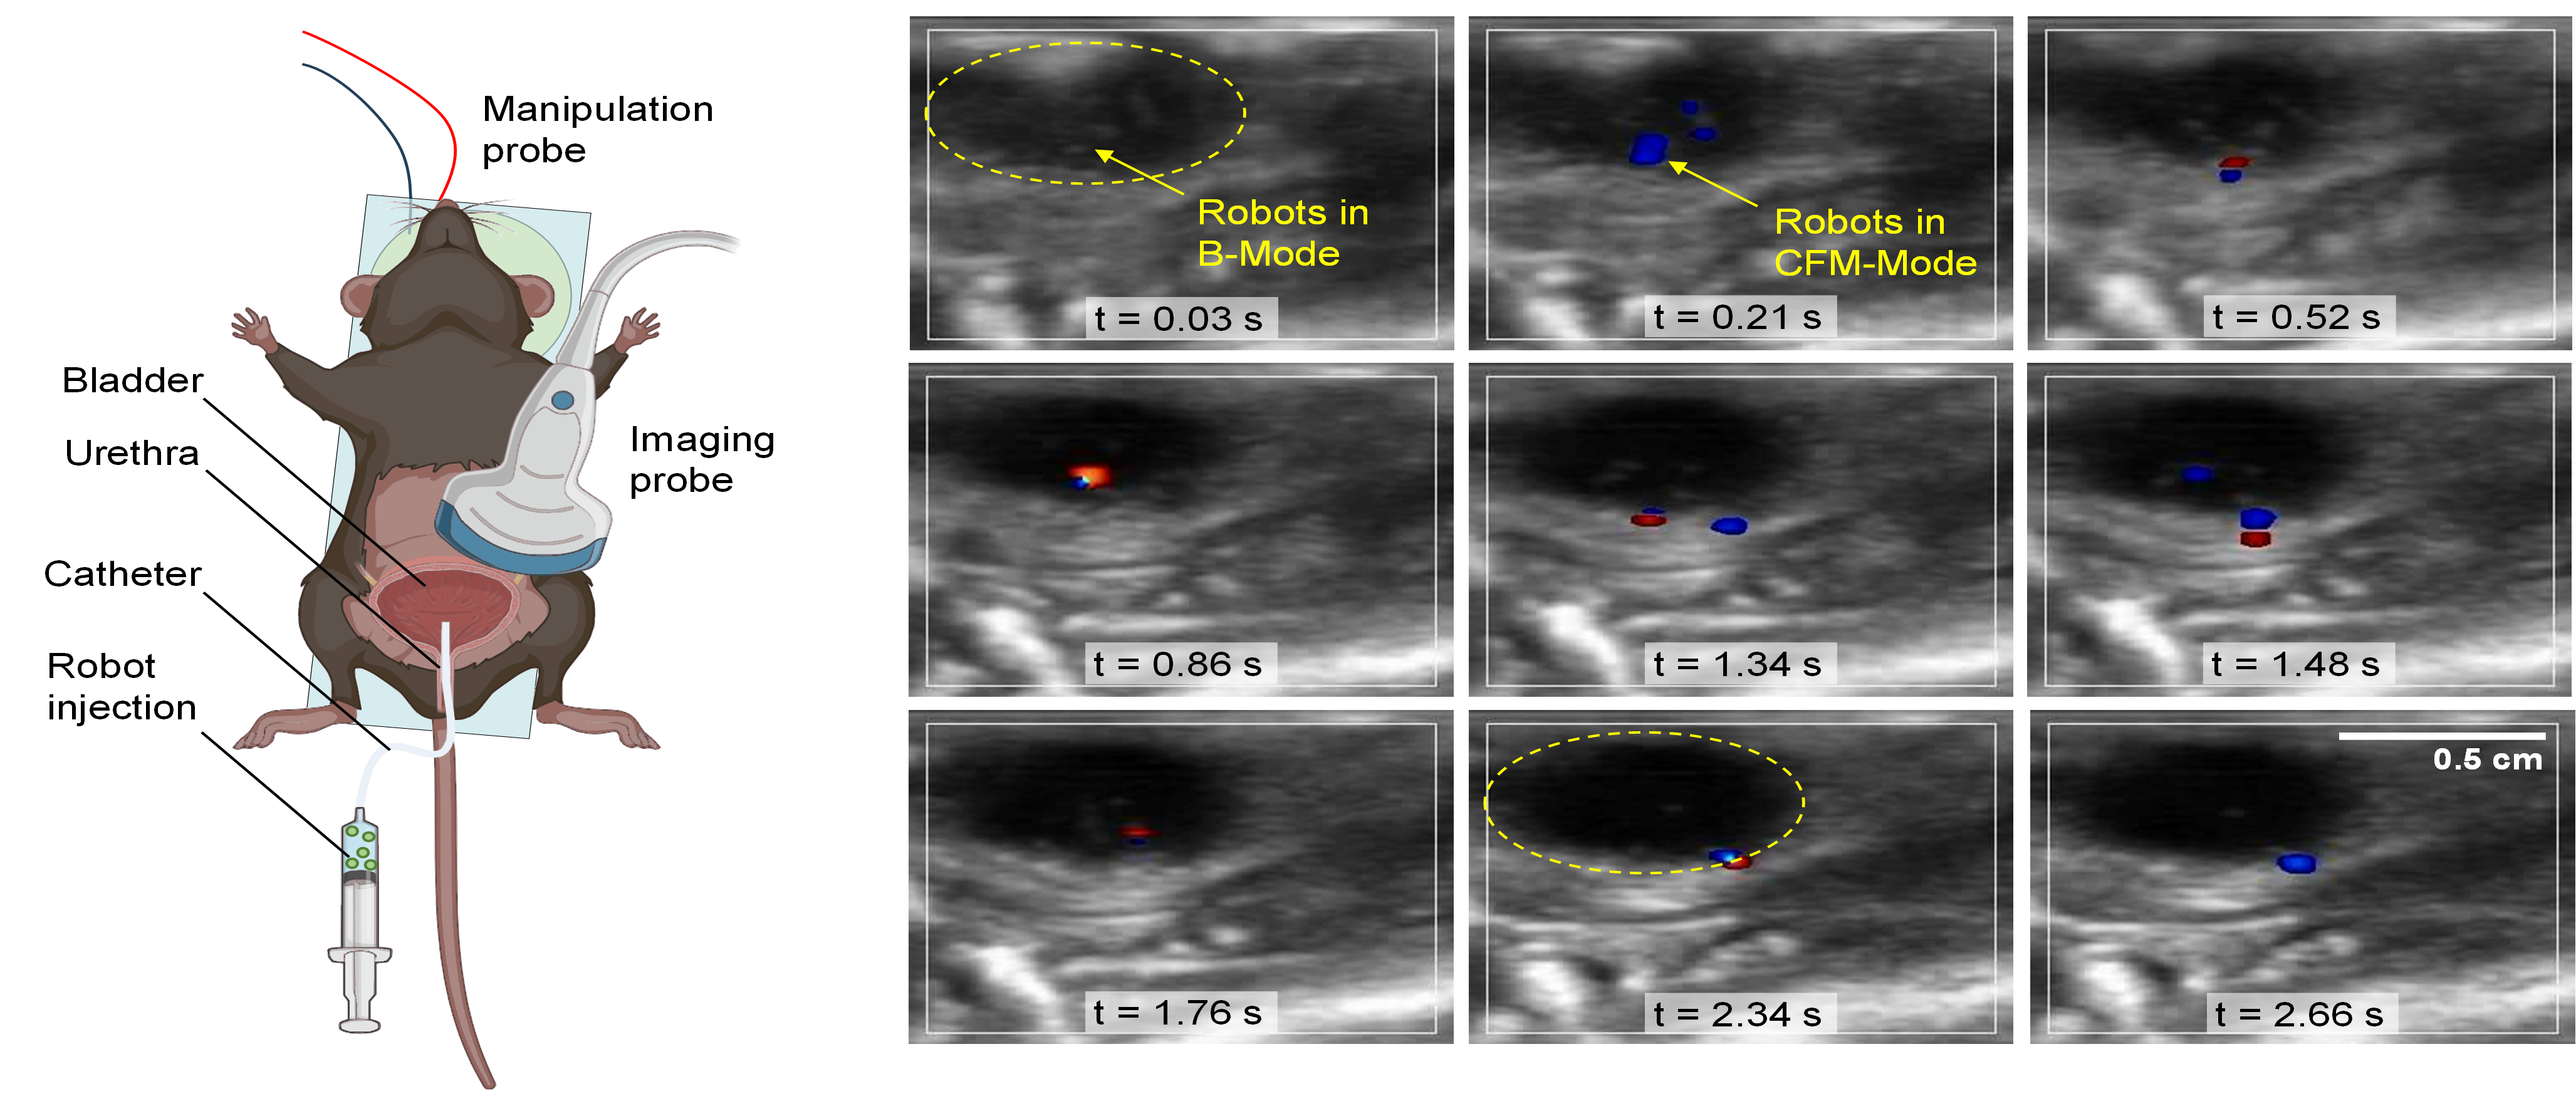

Ex vivo experiment with acoustic microrobots delivered into the bladder via trans-urethral catheterization, and imaged following ultrasound activation

Visualization and tracking of microrobots delivered into mouse bladder

Microrobots capable of being wirelessly manipulated within the human body can revolutionize the future of medicine and offer innovative solutions in non-invasive therapeutics and surgical procedures. In collaboration with Acoustic Robotics Systems Lab, Department of Mechanical and Process Engineering, ETH Zurich, we adapted magnetomotive ultrasound imaging concepts for the real-time visualization of magnetic field-responsive microrobots. The real-time a colored flow map (CFM-mode) ultrasound imaging of individual high acoustic contrast bubble-based microrobots (~73 μm in diameter) was successfully carried out in the ex vivo mouse bladder model, showcasing the potential dual functionality of acoustic microrobots: wireless propulsion with real-time ultrasound imaging.

Dillinger et al., Sci Adv. 2025